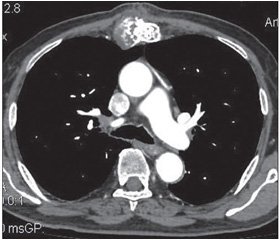

Хондросаркома грудини належить до рідкісних захворювань. З урахуванням нечутливості цих пухлин до опромінення та хіміопрепаратів єдиним можливим радикальним методом лікування хондросарком є їх видалення в межах здорових тканин. Наслідком видалення пухлини грудини є, як правило, великий дефект кісткових структур, що потребує пластики. Найчастіше застосовують алопластичні матеріали, серед яких найкращим є титанова сітка, котру фіксують до ребер металевими лігатурами. Подано випадок пластики тіла грудини після її видалення в пацієнта 74 років. Попередньо пацієнт переніс стернотомію з причини аортокоронарного шунтування. Пухлину в зоні рубця виявлено через два з половиною роки після стернотомії. Проведено резекцію тіла грудини та пластику дефекту за допомогою поліпропіленової сітки, поверх якої фіксовано титанову сітку до ребер окремими стальними швами. Поліпропіленову сітку застосовували для захисту структур середостіння від контакту з титановою сіткою. Післяопераційний період супроводжувався тривалою ексудацією по дренажу, який був установлений у середостіння, що можна було пояснити розлогою травмою та прийомом високих доз дезагрегантів та антикоагулянтів. Пацієнт виписаний у задовільному стані через місяць після операції. При розлогих резекціях грудини потрібна негайна пластика для відновлення каркаса грудної клітки. На сьогодні найкращим матеріалом для пластики вважається титанова сітка. Титановий протез має бути надійно фіксований до прилеглих кісткових структур металевими швами. Адекватне дренування та відповідна антибіотикотерапія є профілактикою відторгнення протеза.

Хондросаркома грудины относится к редко встречающимся опухолям. С учетом нечувствительности этих опухолей к облучению и химиопрепаратам единственным возможным радикальным методом лечения хондросарком является их удаление в пределах здоровых тканей. Следствием таких резекций, как правило, является большой дефект костных структур, который требует пластики. Наиболее часто используют аллопластические материалы, среди которых наилучшим является титановая сетка, которую фиксируют к ребрам стальными лигатурами. Представлен случай из практики пластики тела грудины после его резекции у пациента 74 лет. Предварительно пациент перенес стернотомию по поводу аортокоронарного шунтирования. Опухоль в зоне послеоперационного рубца была выявлена через два с половиной года после стернотомии. Проведены резекция тела грудины и пластика дефекта полипропиленовой сеткой, сверху которой фиксирована титановая сетка к ребрам отдельными стальными швами. Полипропиленовую сетку использовали для предотвращения возможного травмирования структур средостения от контакта с титановой сеткой. Послеоперационный период сопровождался длительной экссудацией по дренажу, который был установлен в средостение, что можно было объяснить обширной травмой и приемом высоких доз дезагрегантов и антикоагулянтов. Пациент выписан в удовлетворительном состоянии через месяц после операции. При обширных резекциях грудины необходима немедленная пластика для восстановления каркаса грудной клетки. На сегодняшний день лучшим материалом для пластики считают титановую сетку. Титановый протез должен быть надежно фиксирован к прилегающим костным структурам металлическими швами. Адекватное дренирование и соответствующая антибиотикотерапия являются профилактикой отторжения протеза.

Chondrosarcoma of the sternum is a rare tumor. Chemotherapy and radiation are not effective in the treatment of these tumors. The only effective treatment is the surgical resection with the wide clear margin. The surgical excision of the sternal tumor results in a large defect of tissue and can lead to instability of the chest wall. This defect must be reconstructed to prevent the violation of the lung function. The skeletal defects with a diameter less than 5 cm can be not reconstructed. The bigger defects must be reconstructed immediately. There are many methods of the reconstruction of the sternum defect. The musculocutaneous flaps, autologous bone transplants, or the alloplastic materials, can be used. There is no ideal prosthetic material. Whereas titanium mash alone or in combination with other materials is the most used. One of the proposed material to restore the defect is the cryopreserved sternum, but the authors prove that this method needs validation. 74-year-old patient diagnosed with the chondrosarcoma of the sternum was admitted to the department of the thoracic surgery of the Lviv regional oncological center. The diagnosis was established by chest computed tomography and the biopsy. Two and half years ago patient underwent the sternotomy during the aortocoronary bypass graft surgery. The tumor in the sternum was detected a half of the year ago, but it was considered as the local osteomyelitis. The treatment was ineffective. After biopsy, the diagnosis of chondrosarcoma was established. After the certain therapy the patient was operated. The wide resection of the body of the sternum was performed. During the procedure, the right pleural cavity was opened. The skeleton defect was repaired using two prosthetic materials. The polypropylene mesh was used as the first layer to protect the heart. It was fixed by the non-absorbable sutures to the wound margin. Upper the polypropylene, the titanium mesh was placed and fixed by the steel sutures to the ribs and the rest of the sternum. The right pleural cavity and the retrosternal space were drained. The pleural drainage tube was eliminated on day 4 after the chest radiology examination. The mediastinal drainage tube was settled on active aspiration and was left until the fluid stopped flowing. It was eliminated on day 16 after surgery. The pain was treated by the non-steroidal analgesics. The patient was discarded one month after the surgery. The control 2 months after surgery showed no pathological signs. The pain disappeared, the physical activity was restored. The surgical treatment of the sternal chondrosarcoma has dual aim. The first one is the adequate resection of the tumor to achieve the clear margin, and the second is the plasty of the tissue defect. To reconstruct a large defect, various surgical techniques and materials can be used. The surgeon must plan the intervention and foresee the difficulties. The type of plastic material can depend of the size of the defect. The surgeon must pay a lot of attention to prevent the infection, which can lead to the rejection of the prosthesis. This can be achieved by the firm fixation of the prosthesis, adequate drainage of the operation field and the antibiotic prophylaxis. Proper analgesic administration, physical exercises, as soon as possible, can accelerate the patient’s recovery.